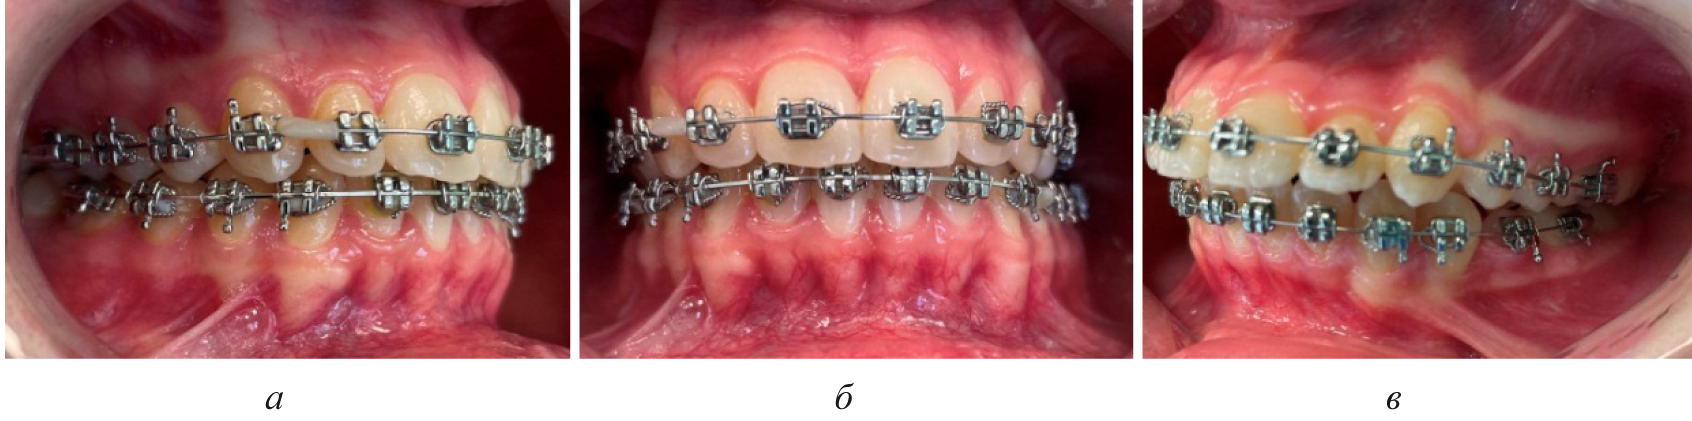

Лечение пациентов, как правило, проводилось с использованием несъемной ортодонтической аппаратуры, в частности эджуайс-механикой.

На первом этапе проводилось раскрытие пространства в области ретенированного зуба и создания условий для его прорезывания. После этого устанавливались элементы аппарата на противоположной челюсти (рис. 4).

Последующие этапы ортодонтического лечения техникой эджуайс проводились с учетом общепринятого протокола и этапности смены металлических дуг, что способствовало нормализации окклюзионных взаимоотношений (рис. 5).

Рис. 5. Окклюзионные взаимоотношения справа (а), спереди (б) и слева (в) на завершающем этапе лечения